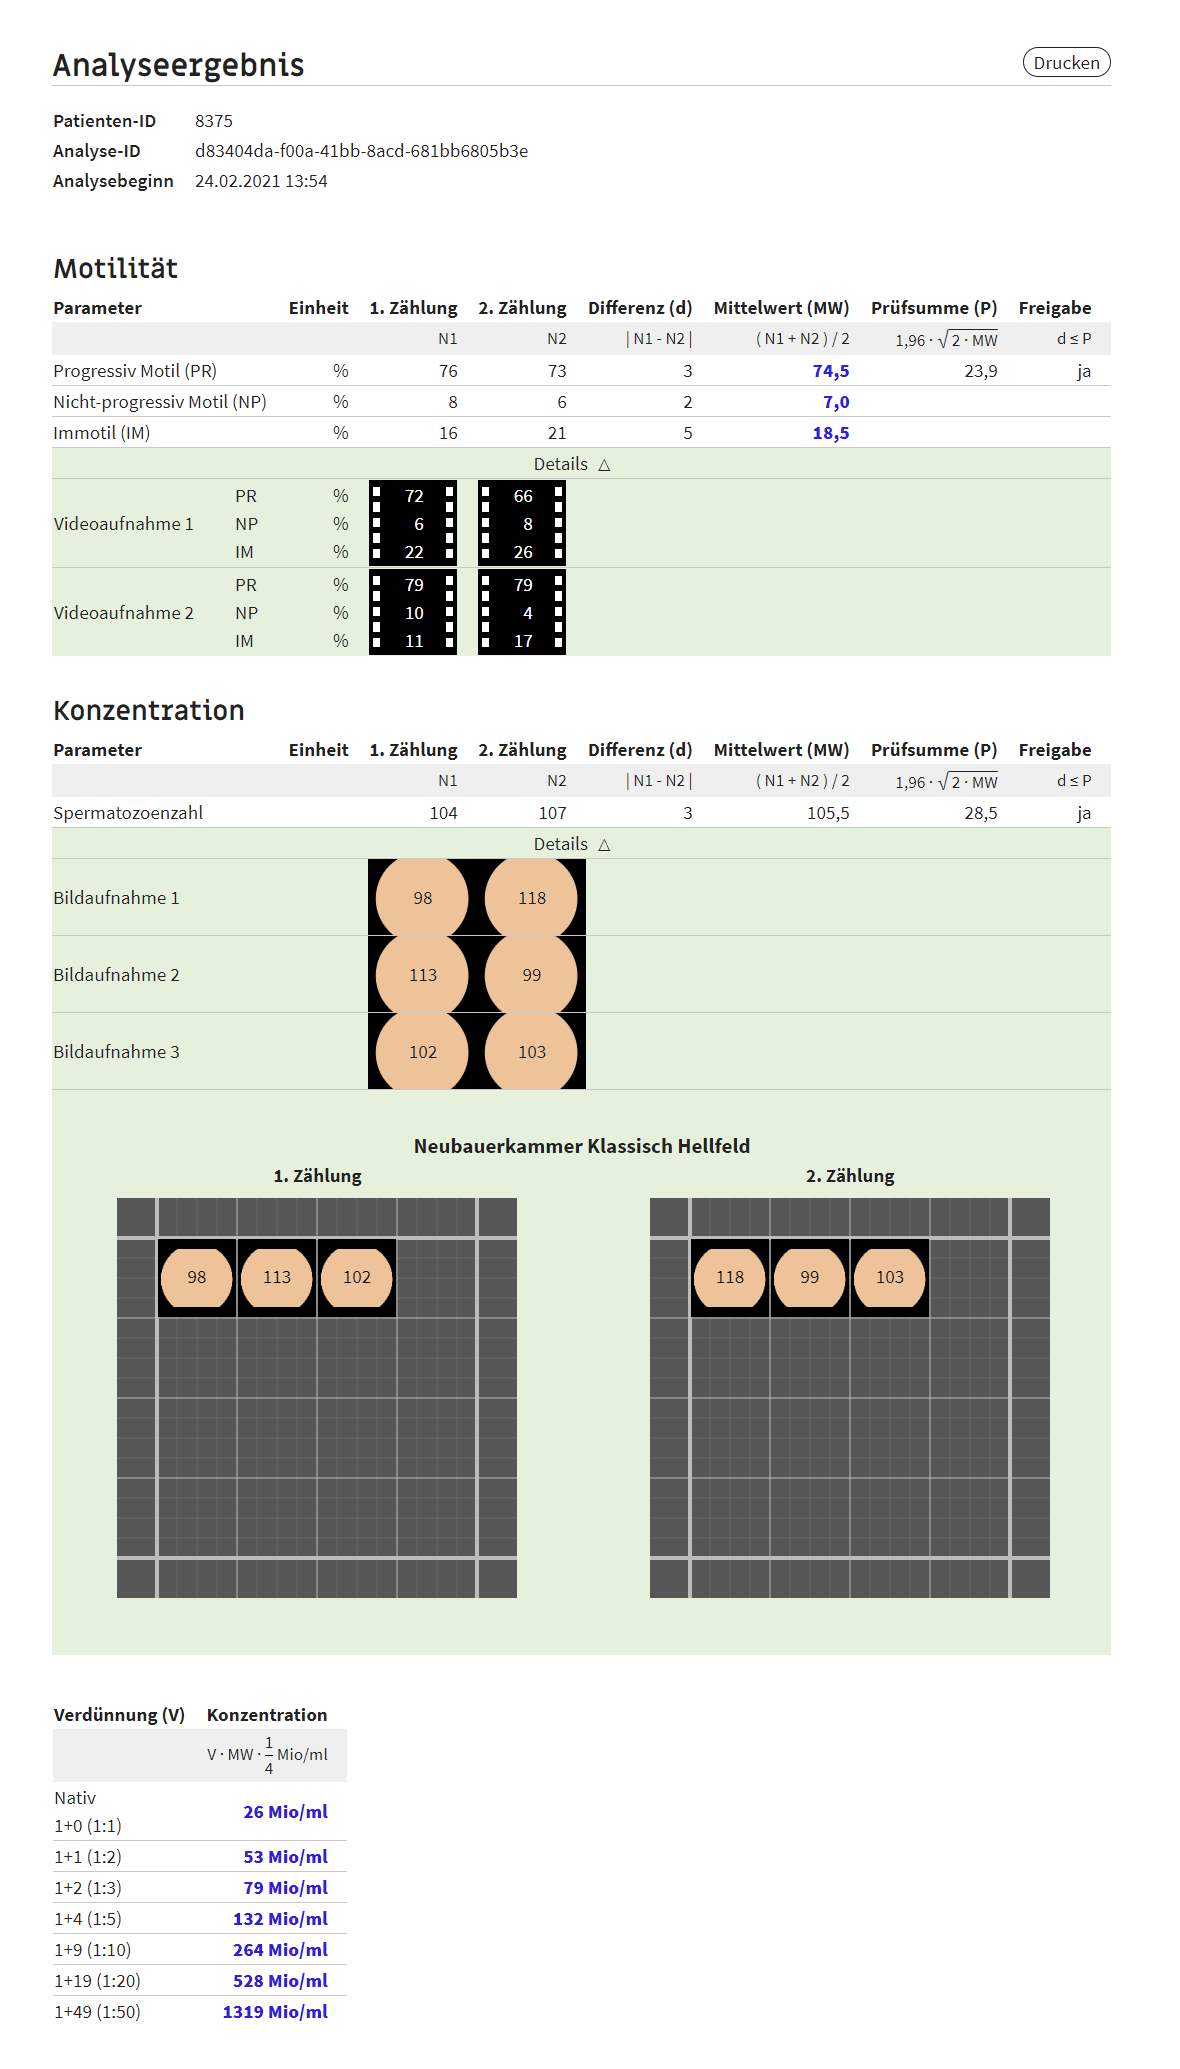

Anhand intelligenter Algorithmen ermöglicht unsere Software zur Spermiogrammanalyse die exakte automatische Bestimmung mikroskopischer Kennzahlen des männlichen Ejakulats: Konzentration, Motilität und bald auch Morphologie

Die Analyse erfolgt nach den Richtlinien der WHO (WHO Laborhandbuch zur Untersuchung des menschlichen Ejakulates, 5. Auflage).

Analyseergebnisse sind unabhängig vom Auge des Betrachters, sondern werden anhand von Referenzwerten objektiv und exakt klassifiziert.

Ãbersichtliche Darstellung der Ergebnisse in der App und als PDF.

Die tensorscope AI Algorithmen ermöglichen eine präzise Auszählung und Bestimmung von Spermien.

WHO-konforme Spermiogramme sind mit wenigen Klicks erstellt, die Abrechnung erfolgt pro bereitgestelltem Datenset.

Der Seminal Analyzer übertrifft manuelle Auswertungsmethoden von Mikroskopanalysen an Effizienz und Genauigkeit

Die Entwicklung erfolgte in enger Zusammenarbeit mit Universitäten, Laboren, Urologen/Andrologen und Reproduktionsmedizinerinnen und unter Berücksichtigung der Richtlinien zur Qualitätssicherung der Spermatologie (RiLiBÃK). Beraten wurden wir durch die Expertise von Barbara Hellenkemper und Prof. Dr. Eberhard Nieschlag.